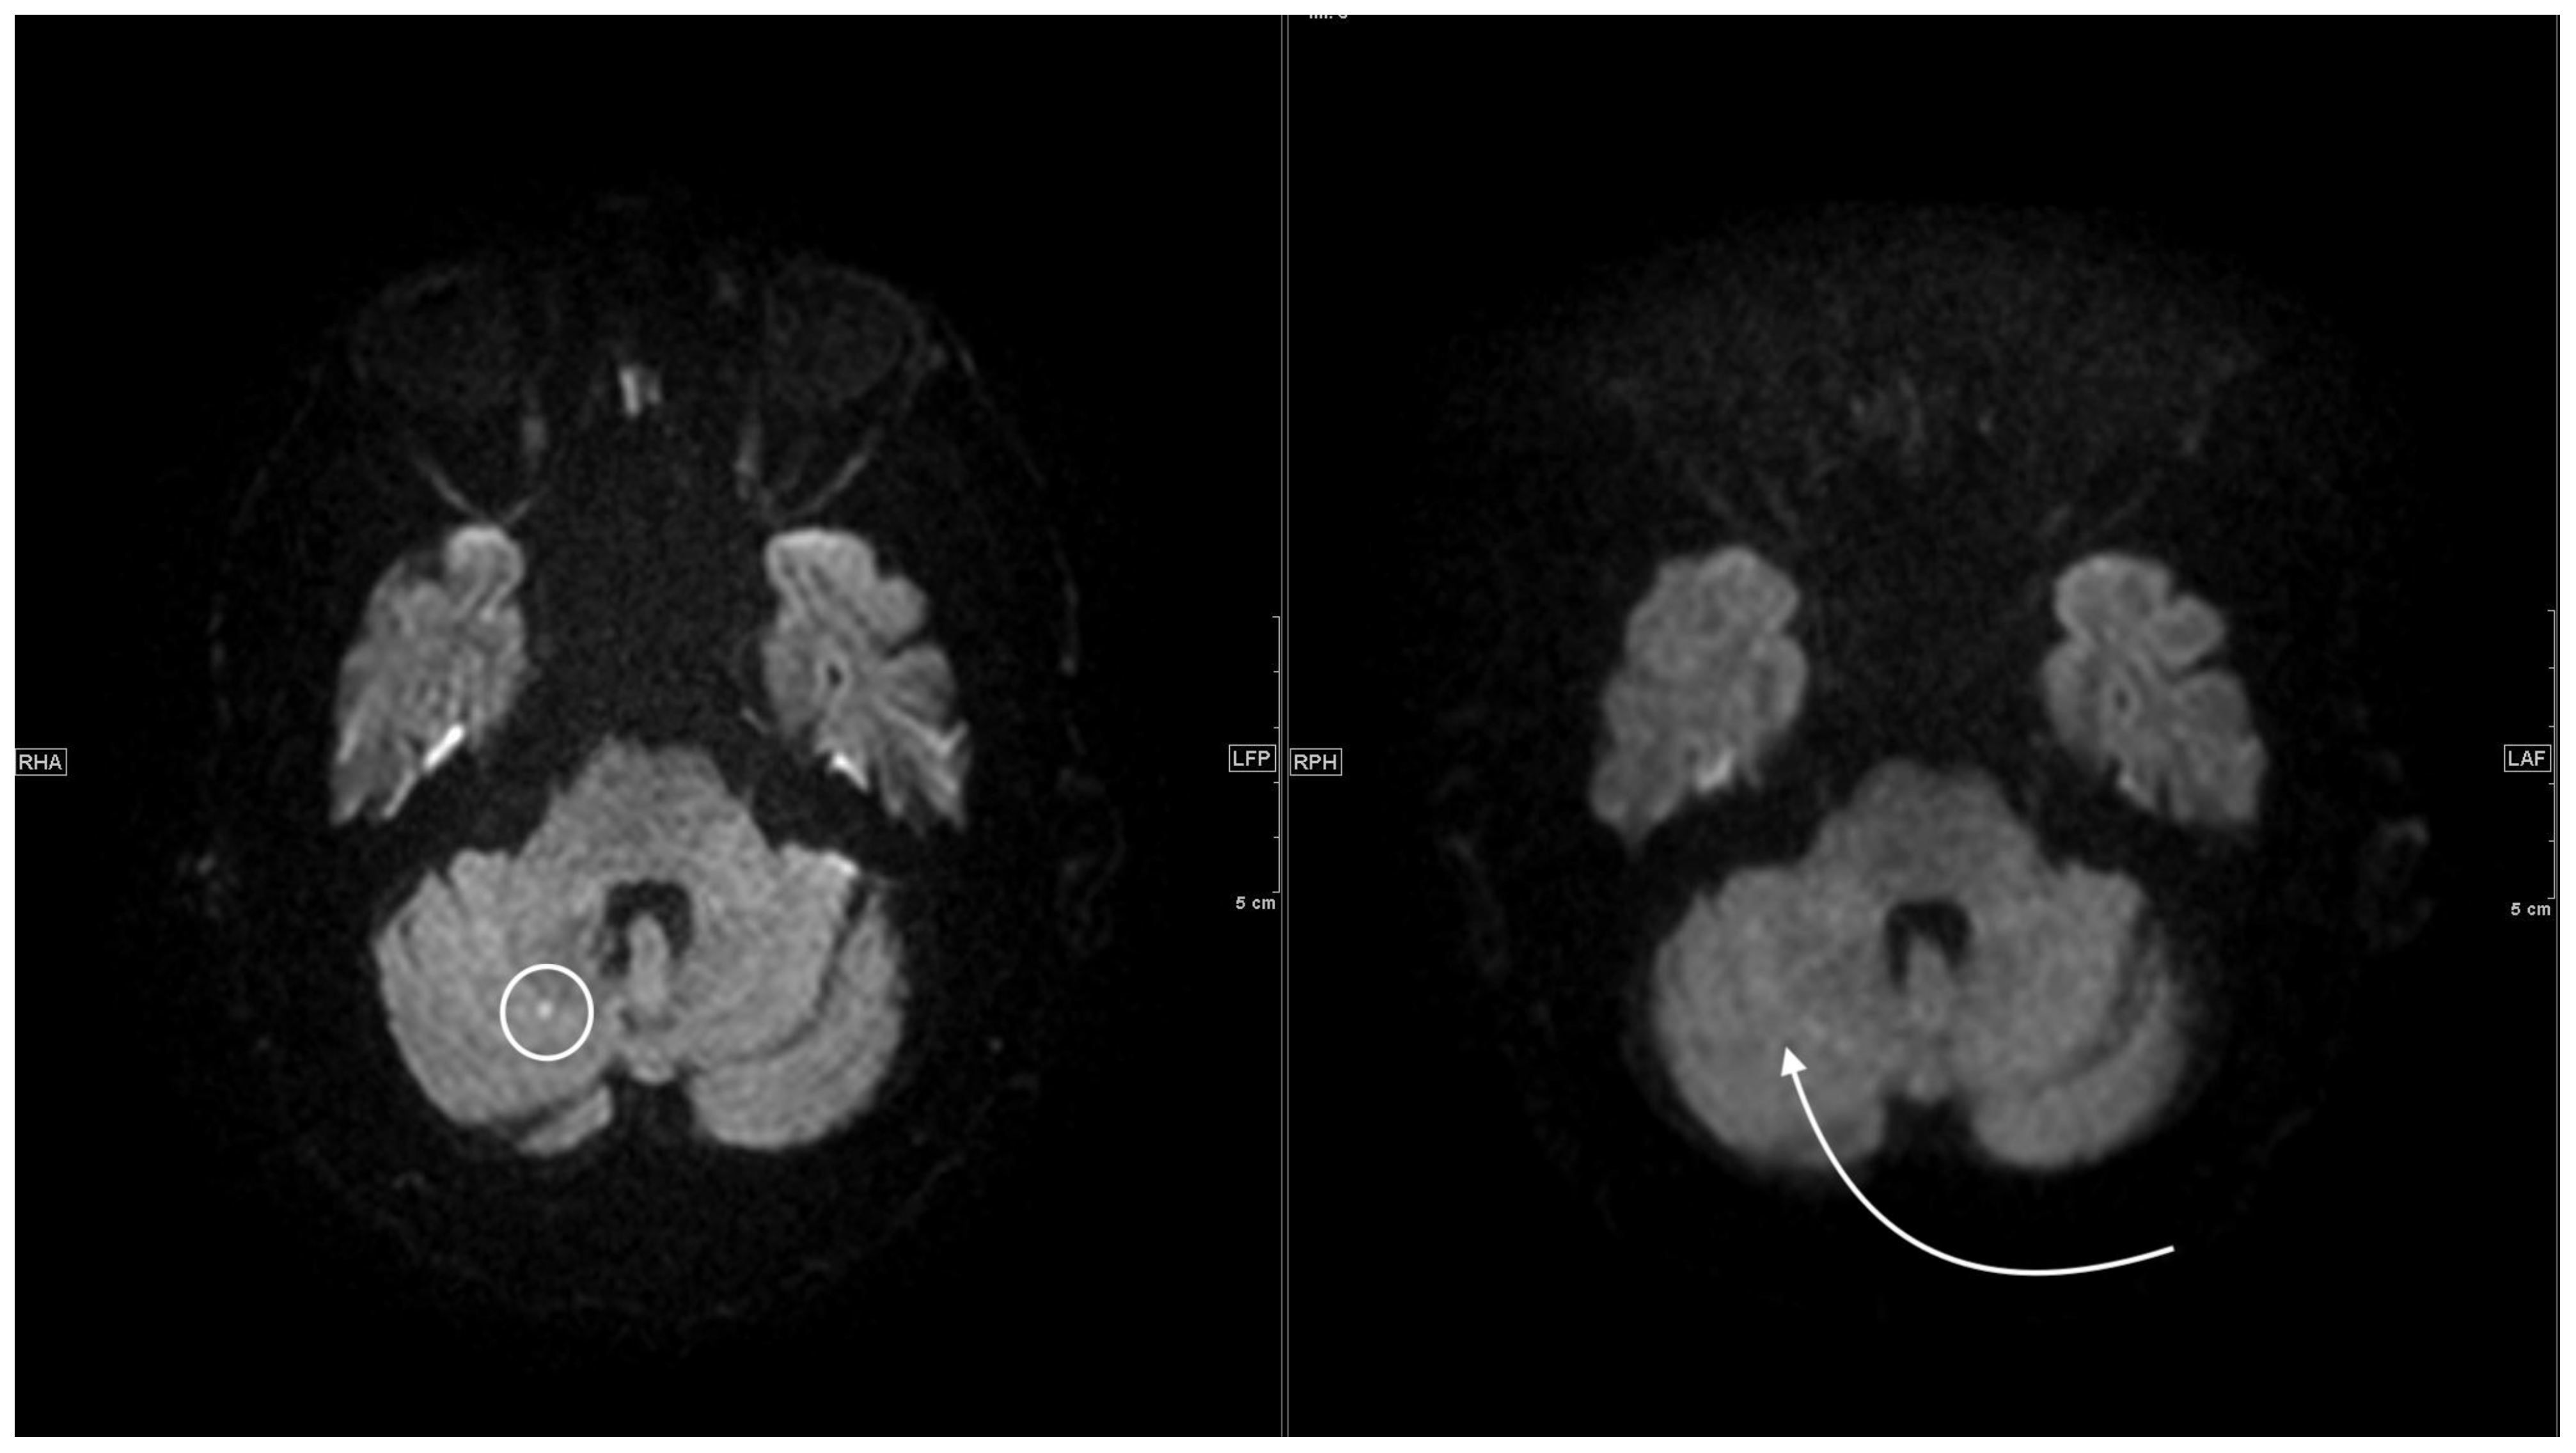

3.1.1. DWI/ADC Datasets

3.2.1. DWI/ADC Datasets